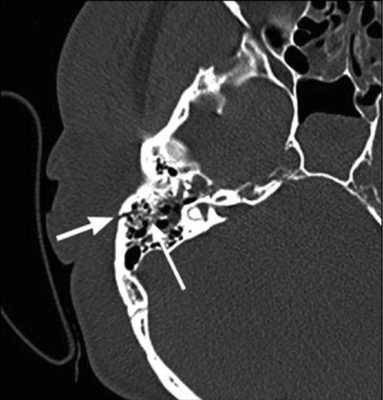

По результатам МРТ головного мозга правая пирамида височной кости деформирована, увеличена в объеме, выполнена субстратом размером до 5,5—2,8—3 см, распространяющимся на область внутреннего слухового прохода, заднего полукружного канала, медиальные отделы барабанной полости, сосцевидный отросток. Описанный субстрат изо-гипоинтенсивен в режиме Т1, гиперинтенсивен — в Т2 и non-EPI DWI (рис. 2). Заключение: признаки рецидива холестеатомы с деструктивными изменениями структур внутреннего и среднего уха на фоне хронических воспалительных изменений.

Рис. 2. Магнитно-резонансная томография головного мозга пациентки М. Деформированная, увеличенная в объеме пирамида височной кости выполнена мягкотканым субстратом.